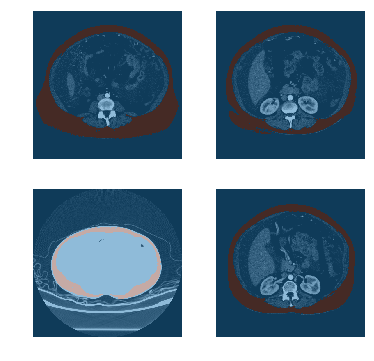

(0028, 0100) Bits Allocated US: 16

(0028, 0101) Bits Stored US: 16

(0028, 0102) High Bit US: 15

(0028, 0103) Pixel Representation US: 1

(0028, 1052) Rescale Intercept DS: "-1024.0"

(0028, 1053) Rescale Slope DS: "1.0"

(7fe0, 0010) Pixel Data OW: Array of 131072 elements